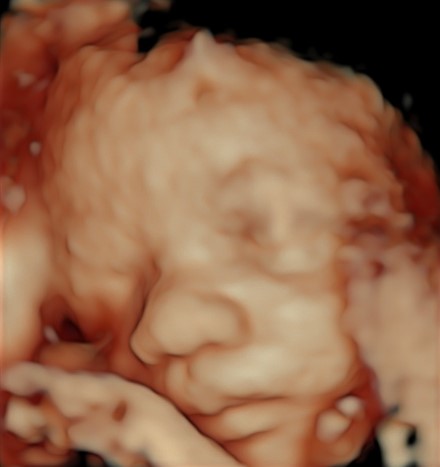

Il tesoro in ecografia è sempre più bello, infatti è da questo mese, ma soprattutto dal prossimo che comincerà ad ingrassare e diventare più tondetto per la gioia degli occhi di babbo e mamma!